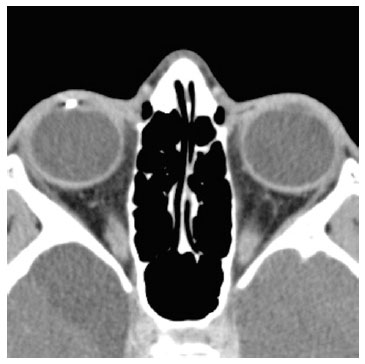

Radiography showed an image suggestive of IOFB, but details could not be assessed. Therefore, computed tomography of the orbits was performed, which provided evidence of a metallic and cylindric IOFB in the anterior chamber topography (Figures 3 and 4).

08-fig04.jpg)